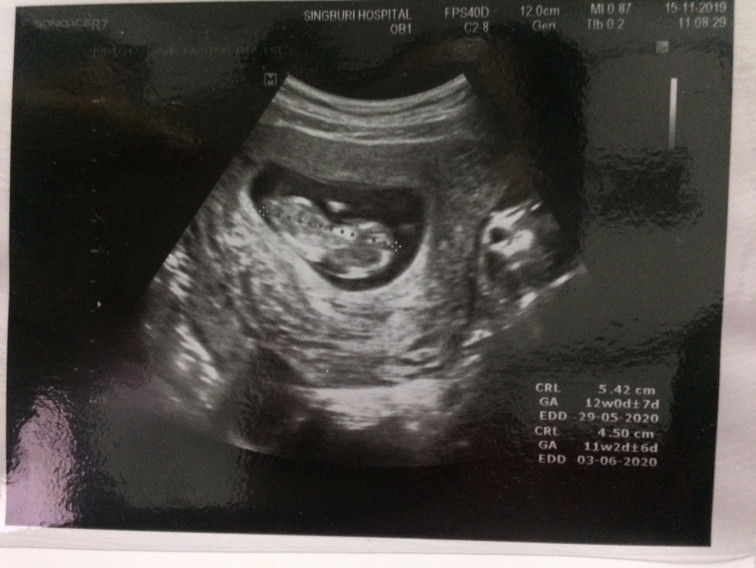

12 วีคค่ะ

12วีค ค่ะ